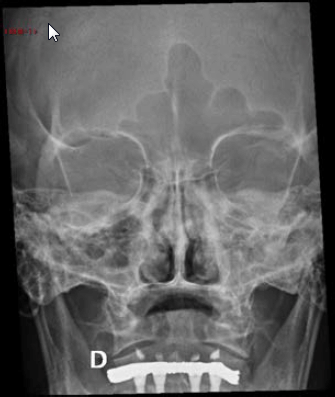

Uma paciente de 60 anos realizou radiografia de seios da face com queixa de cefaleia. Frente às imagens, considera-se que há:

A

sinusopatia aguda, com níveis hidroaéreos nos seios maxilares e velamento de células etmoidais, e doença hipofisária com aumento de volume selar.

B

sinusopatia crônica, com espessamento mucoso nos seios maxilares e células etmoidais, e lesão expansiva da parede posterior do cavum.

C

pólipos nos seios maxilares e células etmoidais, e aumento do espaço articular atlanto-odontoide, provavelmente por artrite reumatoide.

D

espessamento mucoso dos seios maxilares e lesão insuflante do palato, provavelmente por hiperparatiroidismo secundário.

E

sinusopatia aguda, com níveis hidroaéreos nos seios maxilares, e esclerose da asa do esfenoide, podendo corresponder à meningeoma à direita.